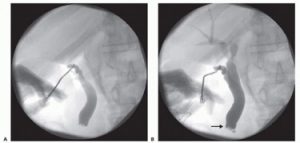

Διεγχειρητική χολαγγειογραφία

Η επόμενη στιγμή είναι η πιο κατάλληλη να πραγματοποιηθεί διεγχειρητική χολαγγειογραφία, προτού δηλαδή διαταμεί ο,τιδήποτε στα εξωηπατικά χοληφόρα. Μεταξύ των ερευνητών δεν υπάρχει ομοφωνία, εάν κατά την διάρκεια της χολοκυστεκτομής θα πρέπει να γίνεται διεγχειρητική χολαγγειογραφία ανεξαιρέτως σε όλους τους ασθενείς ή θα πρέπει να περιορίζεται εκλεκτικά σε ορισμένες μόνο περιπτώσεις. Η πρώτη άποψη στηρίζεται στο γεγονός ότι η διεγχειρητική χολαγγειογραφία διευκολύνει την διασάφηση της ανατομικής κατάστασης των χοληφόρων και αποφεύγεται ο κίνδυνος τραυματισμού των χοληφόρων. Επιπλέον, αποκλείει την παραμονή λίθων στο χοληδόχο πόρο, κάτι που συμβαίνει σε ποσοστό 6 – 8% των ασθενών. Σε αντιδιαστολή, οι θιασώτες της εκλεκτικής διεγχειρητικής χολαγγειογραφίας επισημαίνουν το κόστος της και την παράταση του χειρουργικού χρόνου.

Ο καθετήρας της χολαγγειογραφίας που θα εισαχθεί στον κυστικό πόρο θα πρέπει να είναι πλήρης µε φυσιολογικό ορό και να µην περιέχει αέρα, επειδή οι φυσαλίδες αέρα φαίνονται ως σκιαγραφικά ελλείμματα στην χολαγγειογραφία και δημιουργούν διαγνωστική σύγχυση, με υπόνοια λίθων. Ακολούθως εγχέεται μικρή ποσότητα (2 – 4 mL) σκιαγόνου ουσίας εντός του χοληδόχου πόρου, η πορεία της οποίας παρακολουθείται ακτινοσκοπικά με το ειδικό κυκλοσκόπιο (C-arm). Τα ακτινοσκοπικά ευρήματα αποτυπώνονται σε ακτινογραφικό film την κατάλληλη στιγμή. Με την ακτινογραφία αποσκοπούμε: 1) να απεικονίσουμε τους λίθους στα χοληφόρα, 2) να βεβαιωθούμε για την ανατοµική ακεραιότητα ή την παρουσία ανατομικών ανωμαλιών των εξωηπατικών χοληφόρων, 3) να ελέγξουµε το κολόβωµα του κυστικού πόρου και 4) να παρακολουθήσουμε την ακώλυτη ροή της χολής δια της θηλής Vater προς το δωδεκαδάκτυλο.

Η διεγχειρητική διερεύνηση ή όχι του χοληδόχου πόρου αποφασίζεται σύμφωνα με τα ευρήματα της χολαγγειογραφίας.